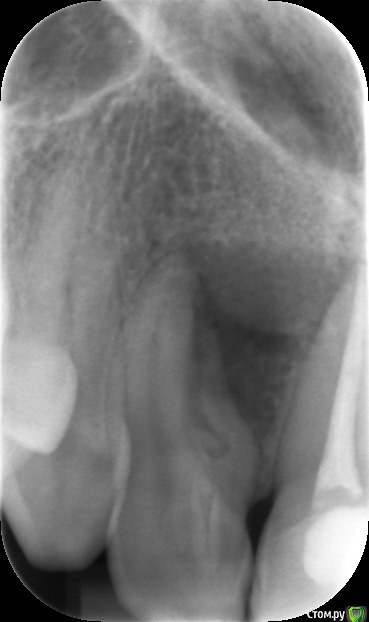

olga1985 Опубликовано 19 августа, 2016 Автор Поделиться Опубликовано 19 августа, 2016 рентген от другого доктора прикладываю Ссылка на комментарий

red_butler Опубликовано 19 августа, 2016 Поделиться Опубликовано 19 августа, 2016 конечно нужен очный осмотр и возможно Кт, но я бы рекомендовал попытаться для начала решить проблему терапевтически. 1 Ссылка на комментарий

Zlata-doctor Опубликовано 20 августа, 2016 Поделиться Опубликовано 20 августа, 2016 эндодонтическое лечение 100%, я бы даже сказала, что надо было сделать до операции. Без этого вообще нет смысла что-то делать с этим зубом Ссылка на комментарий